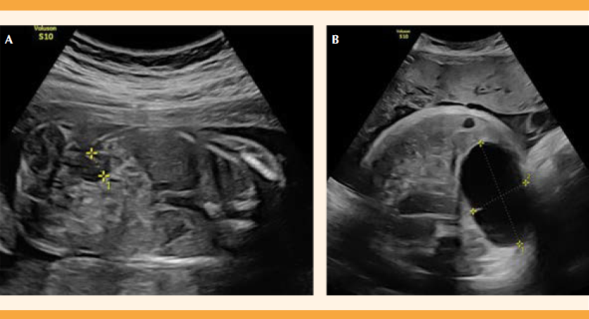

Paciente de 32 años, con un embarazo previo y en el segundo trimestre del actual, con sospecha de un quiste de duplicación intestinal. En la ecografía morfológica de las 20 semanas se sospechó una dilatación del intestino grueso, en su porción derecha, sin otras malformaciones asociadas. El estudio detallado de expertos en patología fetal confirmó la imagen anecoica de 8 mm, no captante de Doppler, a la altura paravesical derecha y polo inferior renal que podía corresponder a una formación quística (Figura 1A).

Figura 1 Estudio prenatal ecográfico. A) Corte ecográfico coronal en la semana 21 + 3 de la gestación. Se observa una lesión anecoica de aproximadamente 8 mm de diámetro, no captante de Doppler, en el flanco derecho a nivel paravesical. B) Corte ecográfico axial del abdomen en la semana 39 + 2 de gestación. Formación quística intraabdominal avascular con tamaño de hasta 64 x 36 mm. Se localiza en el flanco derecho, inferior al polo renal y paravesical, sin contactar con el hígado, la vesícula ni la vejiga.

El estudio genético, mediante amniocentesis, reportó el cariotipo genético y molecular normales y se descartó la posibilidad de fibrosis quística. Esa formación quística tubular avascular, de 27 x 11 x 14 mm se sospechó a las 25 semanas, en la misma localización, debajo de la vesícula, sin contactar con ésta. Con base en esos hallazgos se estableció el diagnóstico de sospecha de duplicación intestinal y se informó a la paciente la fisiopatología, pronóstico y tratamiento de esa lesión, en el que intervinieron, como grupo interdisciplinario, los cirujanos pediatras.

La lesión fue, progresivamente, aumentando de tamaño conforme trascurrían las semanas de gestación de 45 x 20 mm en la semana 32 a 64 x 36 mm en la semana 39 de amenorrea (Figura 1B). Además, en el tercer trimestre se le diagnosticó: diabetes gestacional insulinodependiente, motivo por el que en la semana 39 + 5 se indicó la inducción del parto.